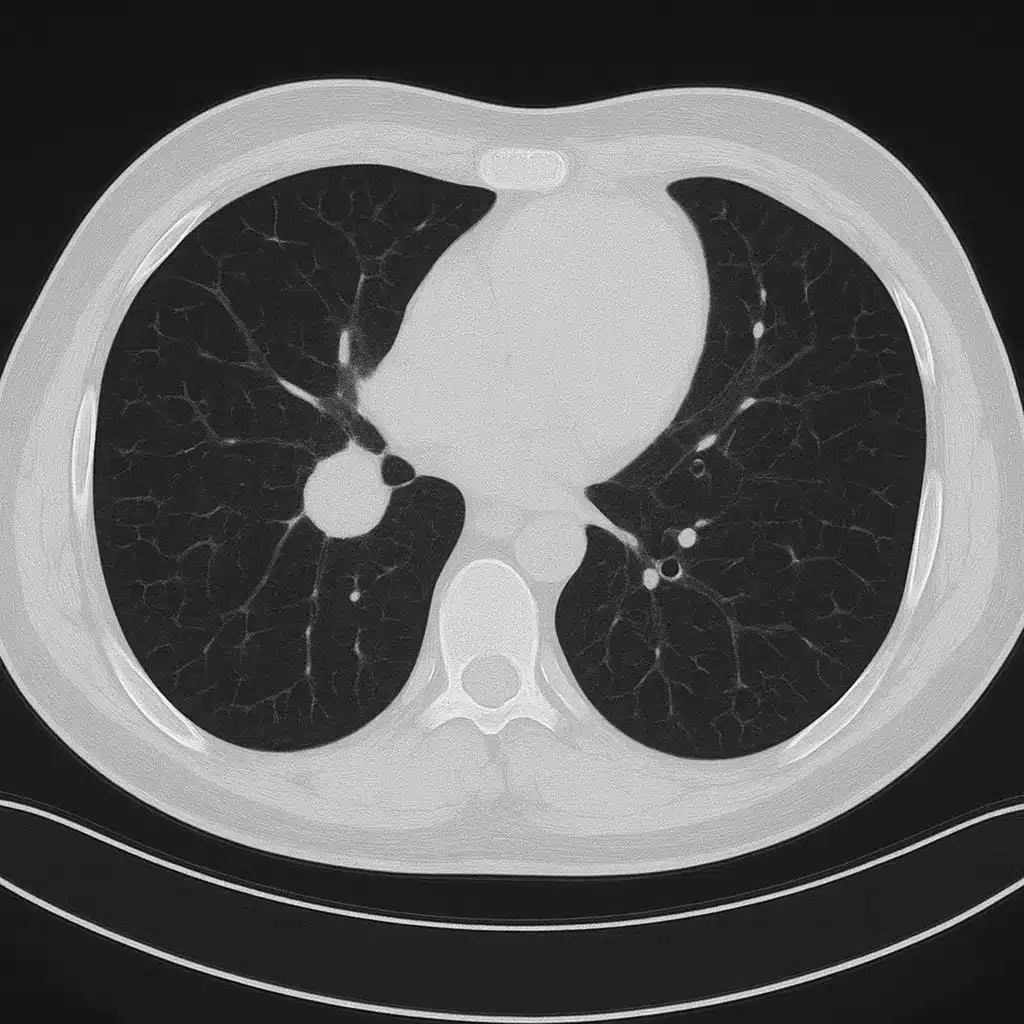

This is a real case from my practice — fully anonymised — where a patient was referred to me for lung-cancer surgery, and I declined to operate. I’ll walk you through the CT images, the clinical reasoning, and what actually happened next.

A patient in their 60s was referred with a 2.2cm lesion in the upper lobe of the right lung.

CT Finding #1: The Nodule Wasn’t Sitting Cleanly

On first look the tumour seemed operable.

On closer inspection, the lesion appeared broad-based against the mediastinum, making dissection riskier and raising suspicion of early invasion.

This alone doesn’t cancel surgery — but it raises the stakes.

CT Finding #3: Hidden Emphysema

The patient’s lung function tests were borderline normal.

But the CT revealed patches of emphysema that would make post-lobectomy breathing significantly harder than the numbers suggested.

This is one of those things that rarely gets mentioned in public writing about thoracic surgery — test results don’t always reflect reality.